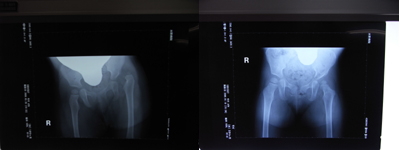

いつもはエコーでの検査ですが今回はレントゲン(立位)でした

鈴木先生の診察では 「いいね~、ちゃんと収まってるよ」 と良い結果で

20090119.jpg

(左:治療前、右:今回のレントゲン)

まだまだ小さい骨頭だけどちゃんと育ってるよ!